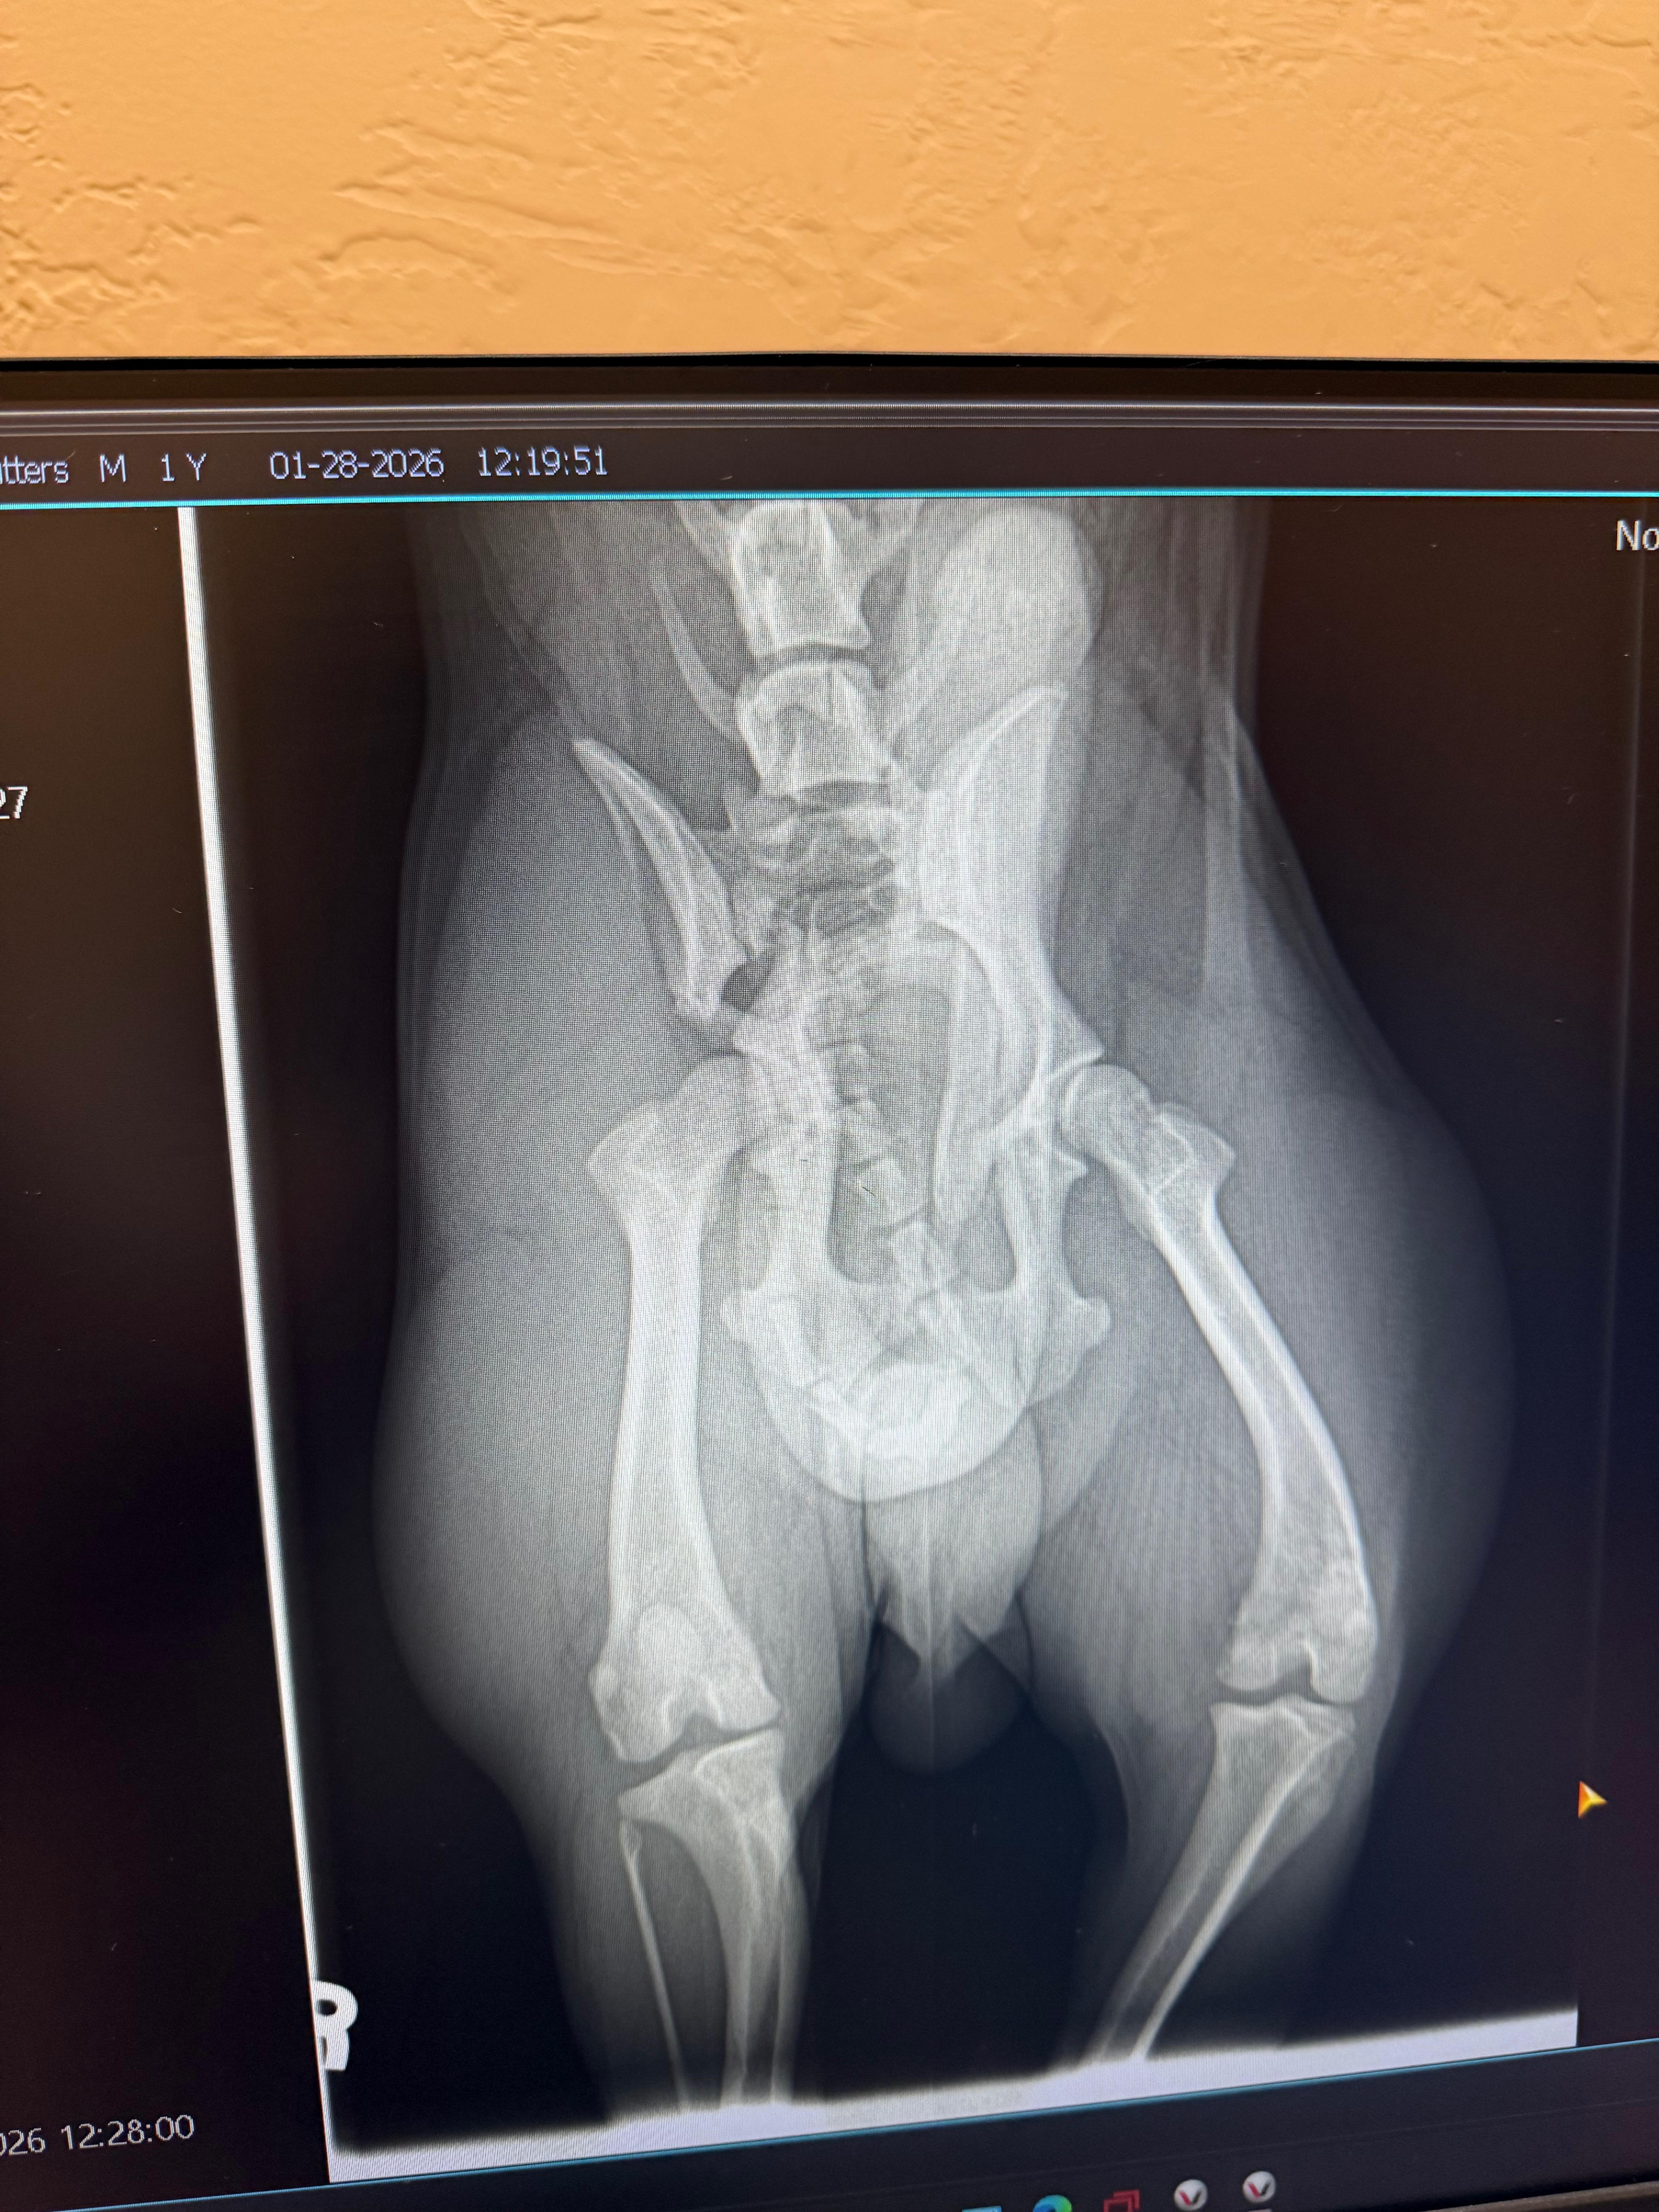

everything I have so he can stay out of pain. He is in need of a surgery that I cannot afford right now I would like him to live a full healthy fulfilled life. I don’t wanna have to put them down my son‘s 11 years old and he loves this dog. I don’t want him to feel the pain of losing him. If you look at the x-ray the left side of his hip you can see how different it is from the right. due to not being able to afford surgery, we have to sedate him with heavy meds and leave them in a kennel and it breaks my heart to see him locked up when all he did was get hurt so we thank you. We love you for whatever you can give or if you need some work done I will donate my time in exchange for help for the surgery.